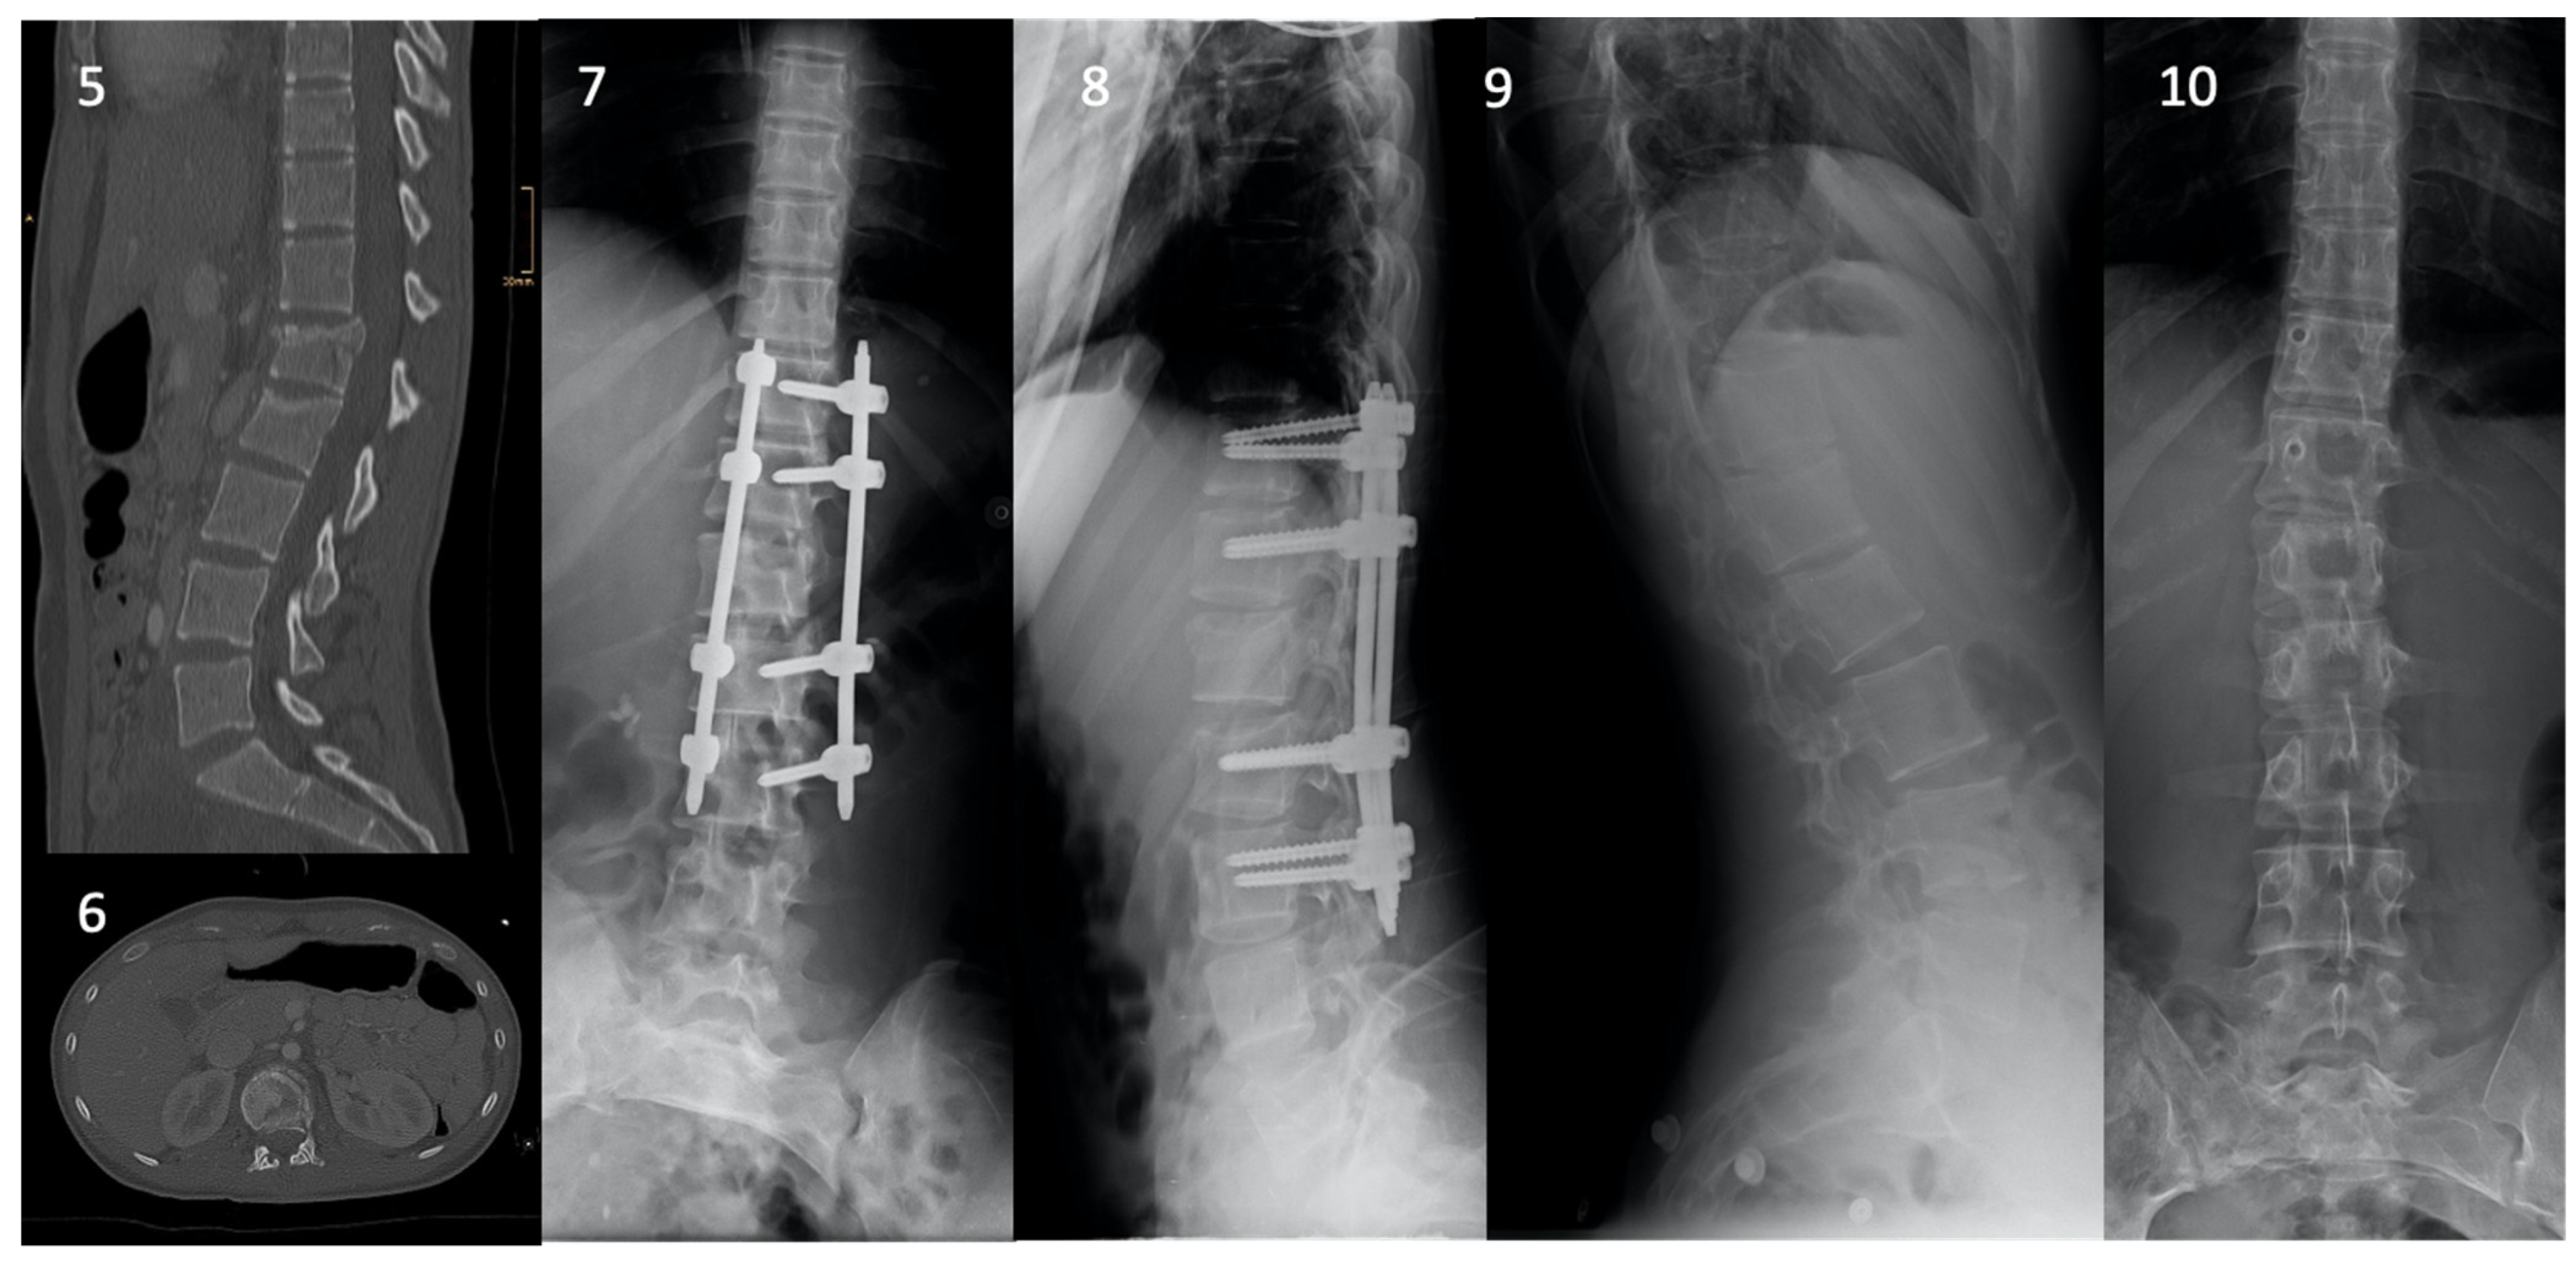

3.2. Fracture Characteristics and Management